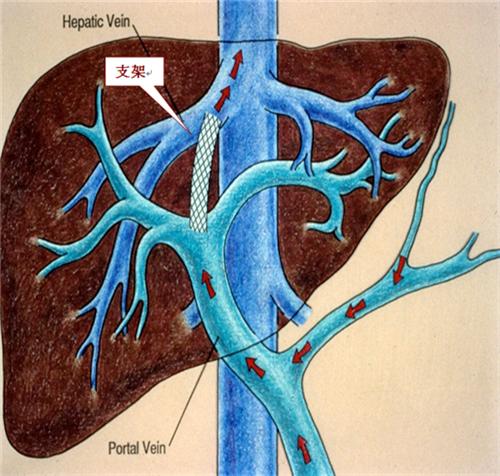

TIPS手术示意图

TIPS术全称为经颈静脉肝内门体分流术(transjugular interhepatic portosystemicstent-shunt,TIPS),是近年发展起来的,并逐步成熟的,用于治疗肝硬化门脉高压、食管胃静脉曲张破裂出血和顽固性腹水的一种手术。TIPS术后门静脉血流可迅速部分分流,门静脉高压即刻得到缓解,其疗效已得到国内外学者广泛肯定。